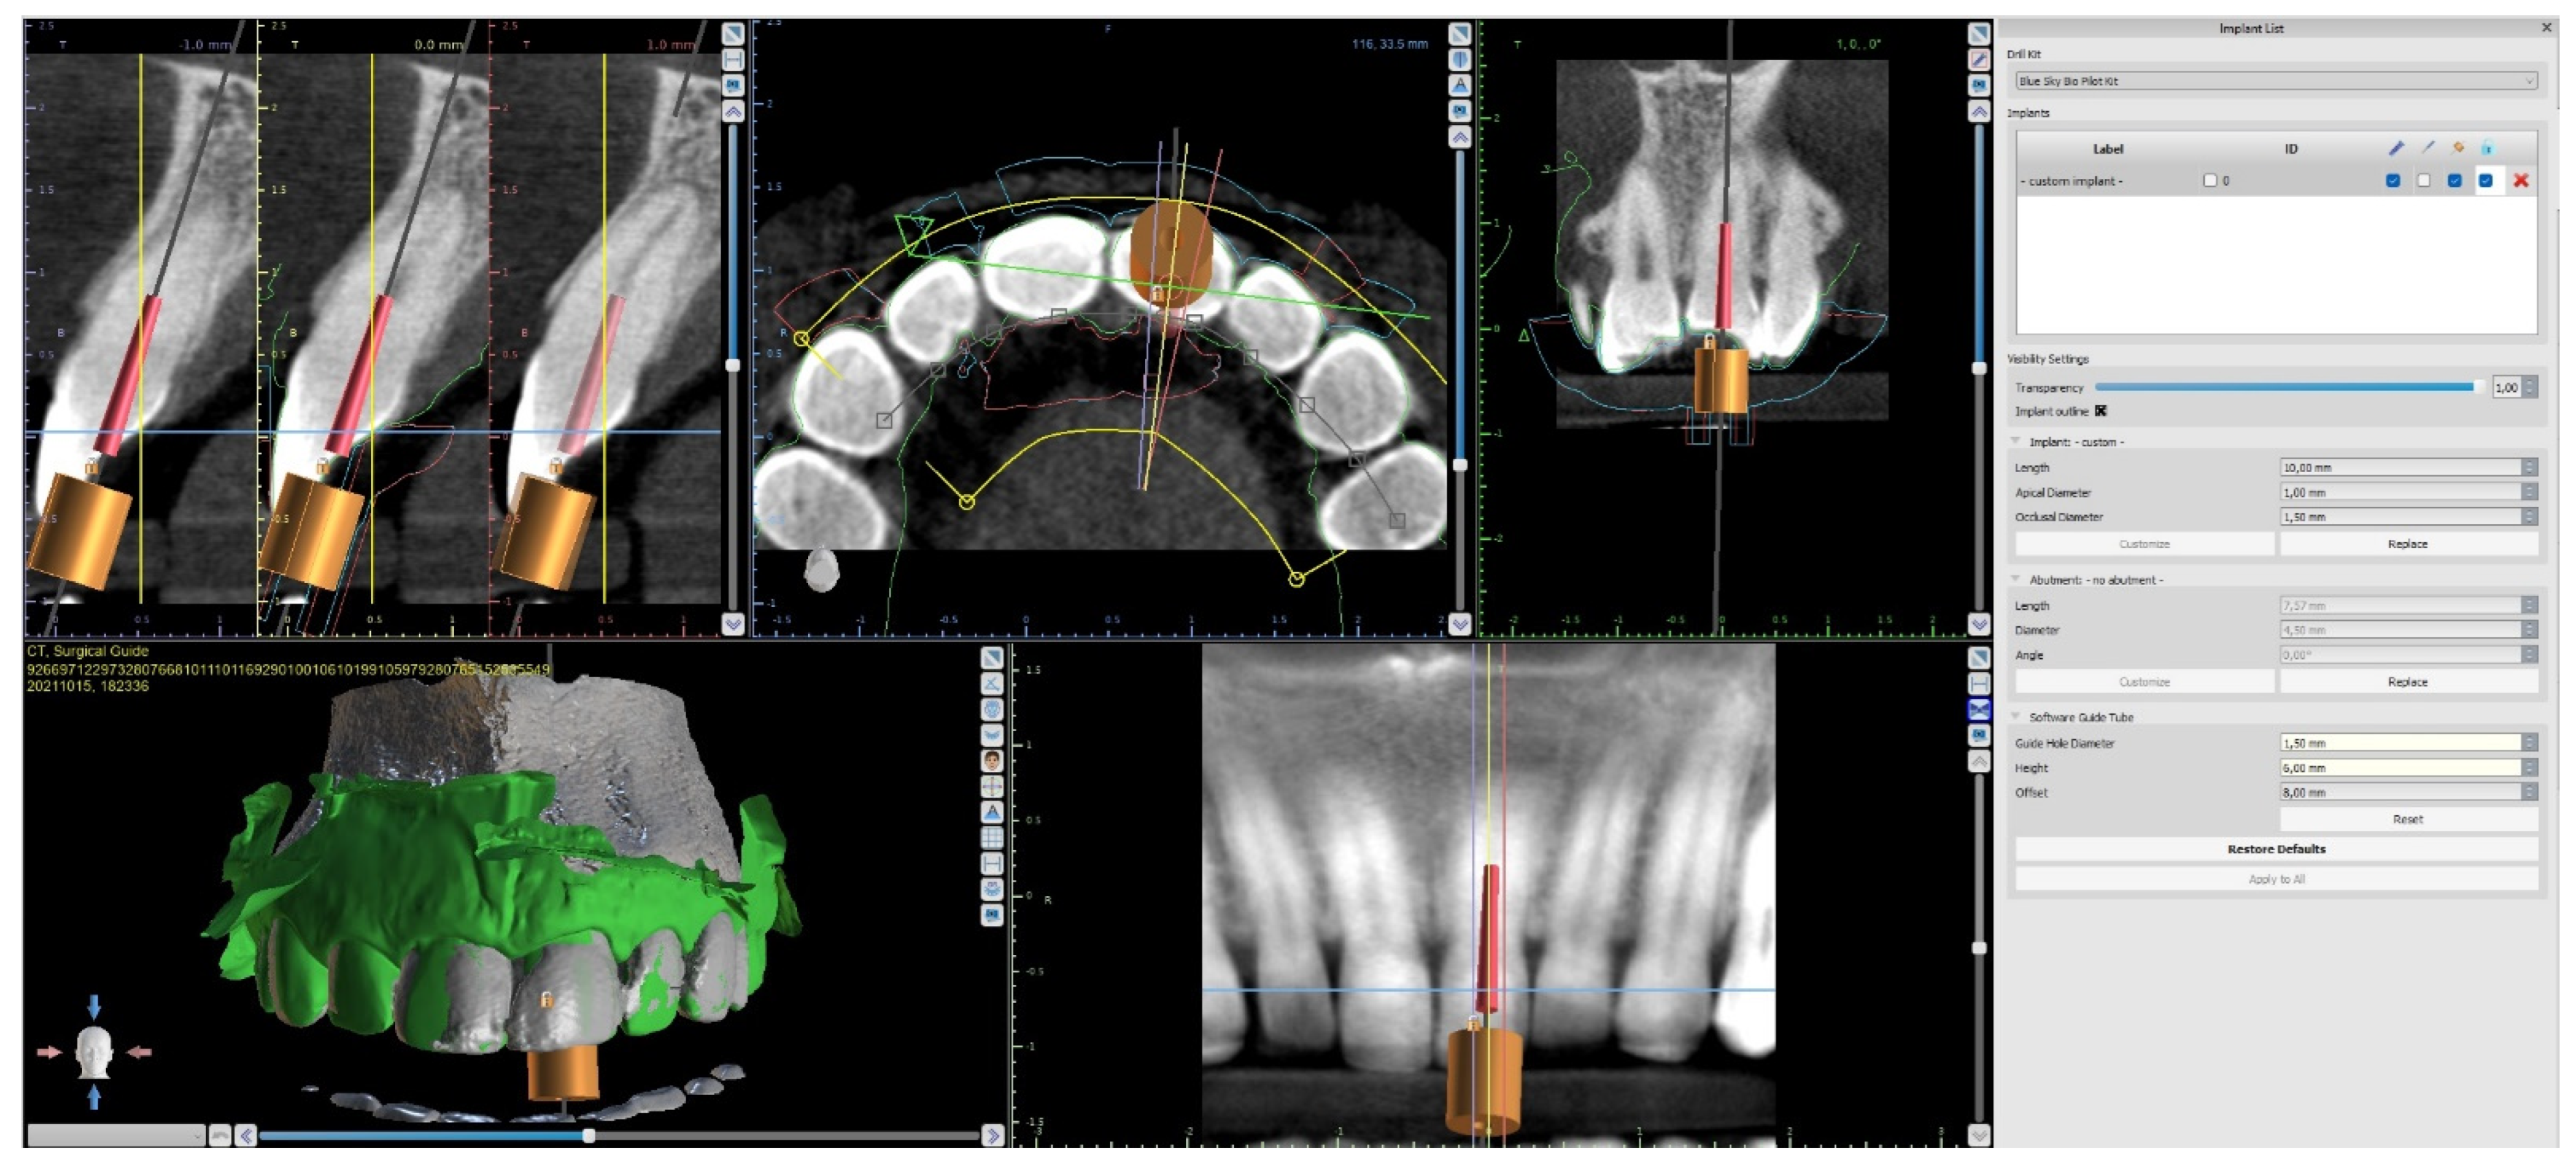

The upper arch was scanned with an intraoral scanner (PrimeScan, Dentsply Sirona) instead of analogue impressions. The STL file of the upper arch and the CBCT images were combined in Blue Sky Plan (Blue Sky Bio). The accuracy of the merging was cross-checked in three dimensions (Figure 9). An individual virtual implant with a diameter of 1.5 mm was used during planning, in accordance with the diameter of the endodontic access tool (Figure 10). The CBCT images allowed us to plan the position of the virtual implant so that the drill apex was located at the top of the visible part of the root canal system [23] (Figure 11).

Figure 10. Figure presenting settings of custom implant in Blue Sky Plan software. Implant length, guide tube height, and offset must be equal to access tool’s working length.

The endodontic guide was planned as in the previous case, using the combined images of CBCT (CS 8100 3D, Carestream, 50 × 50 mm) and the intraoral scan uploaded into the software for virtual planning (Blue Sky Bio). The top of the sleeve was 20 mm from the radiographically visible part of the root canal. The guide sleeve was 6 mm long and 1 mm in diameter (Figure 17).

The guided endodontics demanded more complex planning in this case due to artefacts caused by metal restoration in a neighbouring tooth (the second premolar, tooth 25) and the completely nonvisible root canal. According to Buchgreitz et al., when CBCT does not allow clinicians to visualize the canal, the target point in single-rooted teeth can be established through the centre of the root, as seen in the axial view [25]. Despite the fact that tooth 24 is not a single-rooted tooth, in this case, the virtual drill orientation was defined through the centre of the buccal root. A margin of 2 mm to ensure sufficient root dentine thickness was preserved, as there was no visible part of the root canal. The top of the sleeve was 15.5 mm from the bottom of the tooth chamber. The guide sleeve was 6.5 mm long and 1 mm in diameter (Figure 20). The teeth-supported guide was designed with an embossed canal marking (Figure 21).

As in the previous case, the virtual drill orientation was established in the centre of the root. The top of the sleeve was 14 mm from the bottom of the tooth chamber. The guide sleeve was 6 mm long and 1 mm in diameter (Figure 26). The template with engraved canal markings was equipped with a window for assessing the correctness of the guide’s intraoral placement (Figure 27). The buccal canal was cautiously negotiated through the guide with a size 10 file (C-Pilot #10) instead of rotated burs. The root canal orifice was reached at a length of 15 mm from the top of the guide sleeve. The time needed to localize the canal path in this case was approximately 10 min. The file was taken to the working length and a conventional root canal treatment followed (Figure 28).

Root canal treatment in teeth with calcified canals should be performed if the tooth presents radiological signs of periapical disease or if symptoms are reported by the patient (e.g., pain, tenderness to percussion, etc.)—or before prosthetic or surgical treatment. The endodontic procedure should be carefully planned and performed to avoid deviation from the original canal path, root perforation, and excessive loss of tooth structures. Severe calcification or a complex anatomy of the tooth may pose a problem or induce stress, even for a very experienced clinician. The guided endodontic technique has been reported by some authors as beneficial when localizing calcified canals [14,15,18,19,25,26]. Moreno-Rabie et al. [25] performed a systematic review of the studies on the clinical application, accuracy, and limitations of guided endodontics, which revealed that this method is highly accurate and successful, though there is a need for further research. In the case reports presented in this paper, the guided endodontic technique allowed the clinicians to perform a root canal treatment in a minimally invasive manner, protecting the tooth structure. The time needed to localize the canal path was reduced to 10 min in Patients B and D and to 15 min in Patient C (time measured from the administration of local anaesthesia to the confirmation of the path with the electronic apex locator). In Patient A, the time was longer as it was the first learning case, and the procedure took approximately 50 min. The reduced amount of time in cases B–D could have also been attributable to the previously prepared chamber access. Buchgreitz et al. reported that the previous attempt to negotiate the root canal led to the greatest number of optimal precision scores following drill path preparation [24]. Even though the time needed for planning may be perceived as a disadvantage, it eventually significantly reduces treatment time and stress. The STL file of the intraoral scan and the DICOM files of CBCT are needed to design an endodontic guide. These files must be combined in a dedicated software product, e.g., Blue Sky Plan. It is important to separate the lower and upper teeth when performing CBCT examinations in order to make DICOM and STL matching possible. Planning with the use of the multi-sectional view makes it possible to access the root canal and avoid the degradation of the incisal edge or other anatomical structures of the tooth by changing the orientation of the long axis of the virtual implant. However, it is important to bear in mind the possible inaccuracy of CBCT examinations and plan the pathway for the endodontic instruments with a margin ensuring sufficient root dentine thickness [24]. The longer the guide sleeve, the lower the risk of a lateral deviation of the endodontic access tool near the apex of the virtual implant. Resin is a material with greater flexibility than metal, so the use of metal sleeves may also increase the precision of the access preparation. Metal sleeves are recommended especially in cases with thin root canal dentine walls. Placing a metal sleeve and using an adapter bur may protect the resin guide. During the treatment, multiple teeth must be isolated at once with a rubber dam to achieve guide stability. Due to the short, thick crowns, placing the guide with the rubber dam was much more difficult in Patient A than it was in Patient B, and the guide had to be shortened to achieve better stability. The described technique was limited to straight parts of root canals. Difficulties with using a guide technique may occur in patients with restricted mouth opening or in posterior teeth [2]. Exclusion criteria may also include metal restorations in the adjacent teeth, as this leads to CBCT artifacts in the area of interest [24]. The main disadvantage of guided endodontics may be the additional cost of procedures and materials such as CBCT, 3D printers, and resin. The guided technique can also be used when removing fiberglass posts [25,27,28] or during the treatment of teeth with developmental anomalies, e.g., dens invaginatus [29,30] or dentin dysplasia [31]. In the four presented cases, all calcified root canals were properly treated using endodontic guides. The CBCT examinations were performed according to the guidelines of the European Society of Endodontology [32]. A summary of the procedure is shown in Table 1.